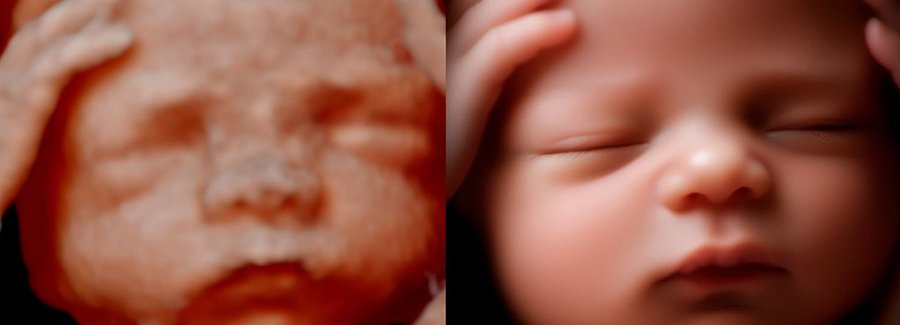

Often referred to as 5D, HD or FRV (fetal realistic view), 5D/HD is the newest development in pregnancy imaging. It captures and combines high definition volume data to create automated images with amazing color and clarity so you can see your baby as though you were looking from inside the womb.